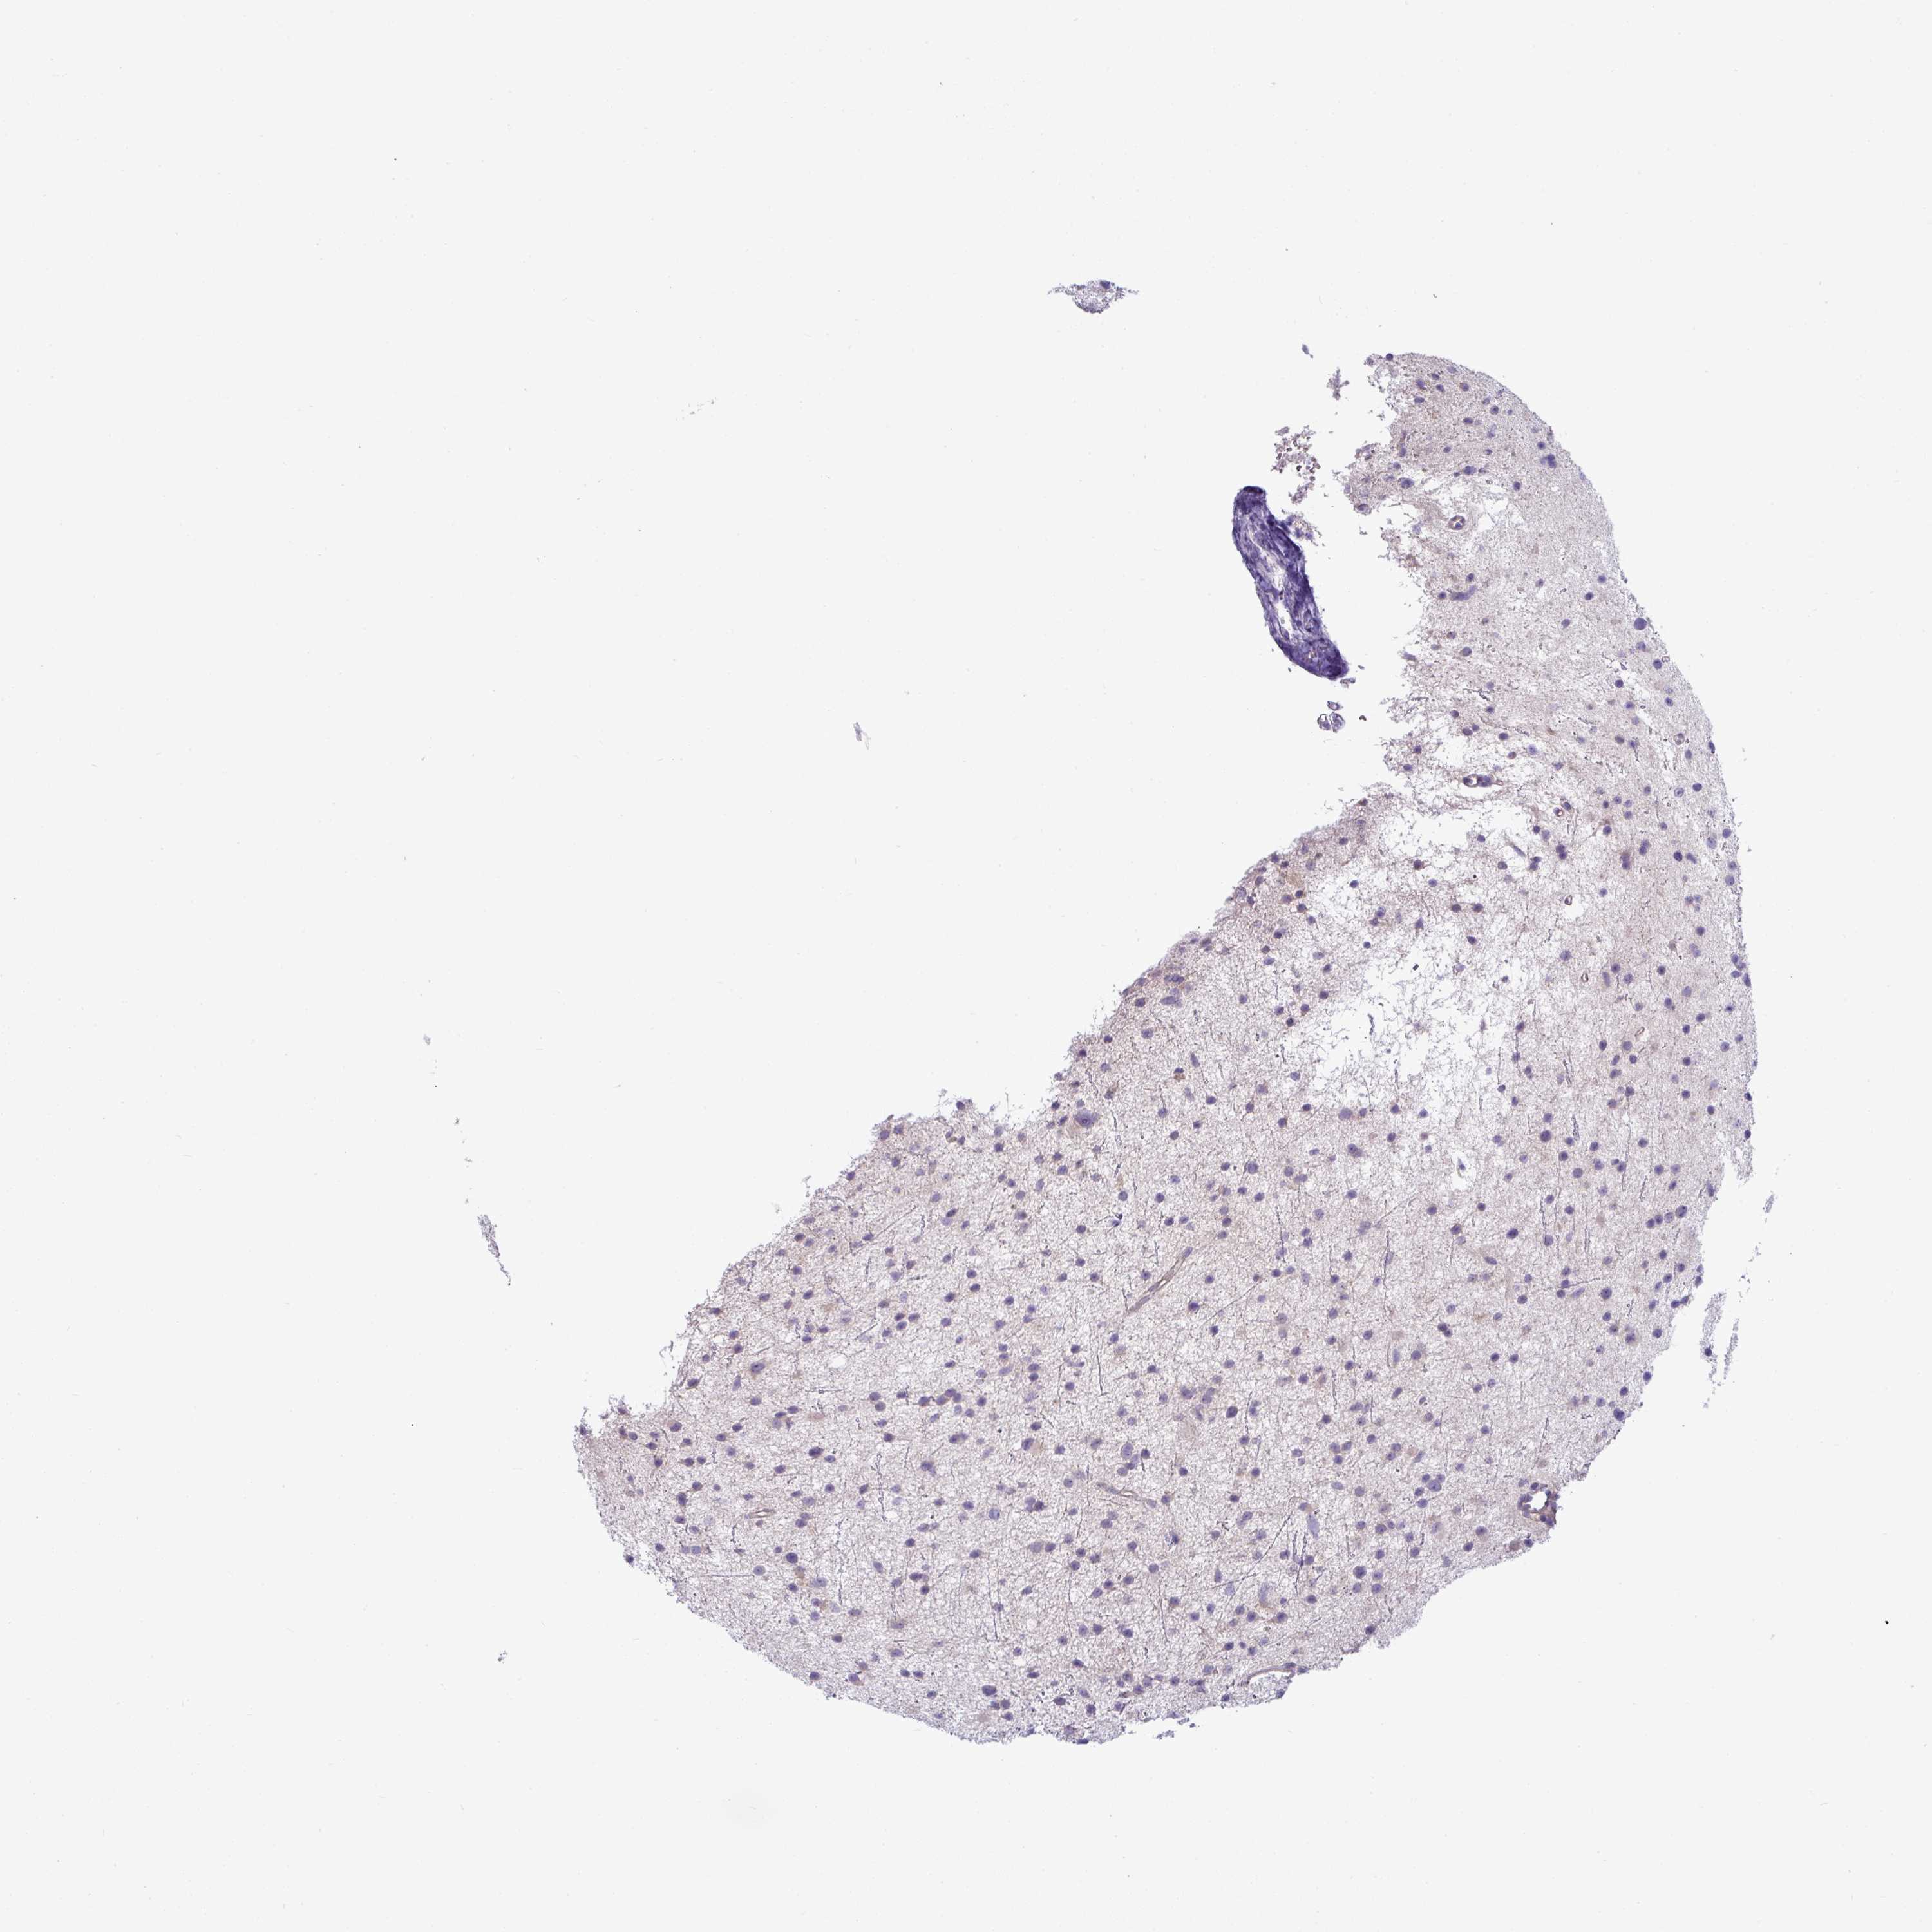

GLIOMA - Protein expressioni

A mouse-over function shows sample information and annotation data. Click on an image to view it in a full screen mode. Samples can be filtered based on level of antibody staining by selecting one or several of the following categories: high, medium, low and not detected. The assay and annotation is described here.

Note that samples used for immunohistochemistry by the Human Protein Atlas do not correspond to samples in the TCGA dataset.

Antibody stainingi

Antibody staining in the annotated cell types in the current human tissue is reported as not detected, low, medium, or high, based on conventional immunohistochemistry profiling in selected tissues. This score is based on the combination of the staining intensity and fraction of stained cells.

Each image is clickable and will lead to virtual microscopy that enables deeper exploration of all samples and also displays staining intensity scores, fraction scores and subcellular localization as well as patient and tissue information for each sample.

Antibody HPA049317

Staining

High

Medium

Low

Not detected

Intensity

Strong

Moderate

Weak

Negative

Quantity

>75%

75%-25%

<25%

None

Location

Nuclear

Cytoplasmic/membranous

Cytoplasmic/membranous,nuclear

Glioma, malignant, High grade

Glioma, malignant, Low grade

Glioblastoma, NOS